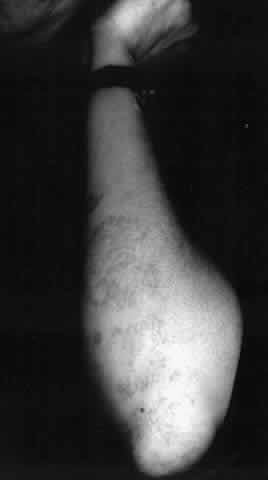

Epidermolysis bullosa dystrophica is characterized by scarring of the skin over limbs, hands, and feet. The scars become keloidal, resulting in deformities of the limbs, hands, and feet; these are most severe in the dysplastic form (Fig. 17). The most severe involvement of mucous membranes also occurs in the dysplastic, recessive form of epidermolysis bullosa dystrophica.106

Fig. 17. Epidermolysis bullosa dystrophica. (Courtesy of Dermatology Service, WRAMC)